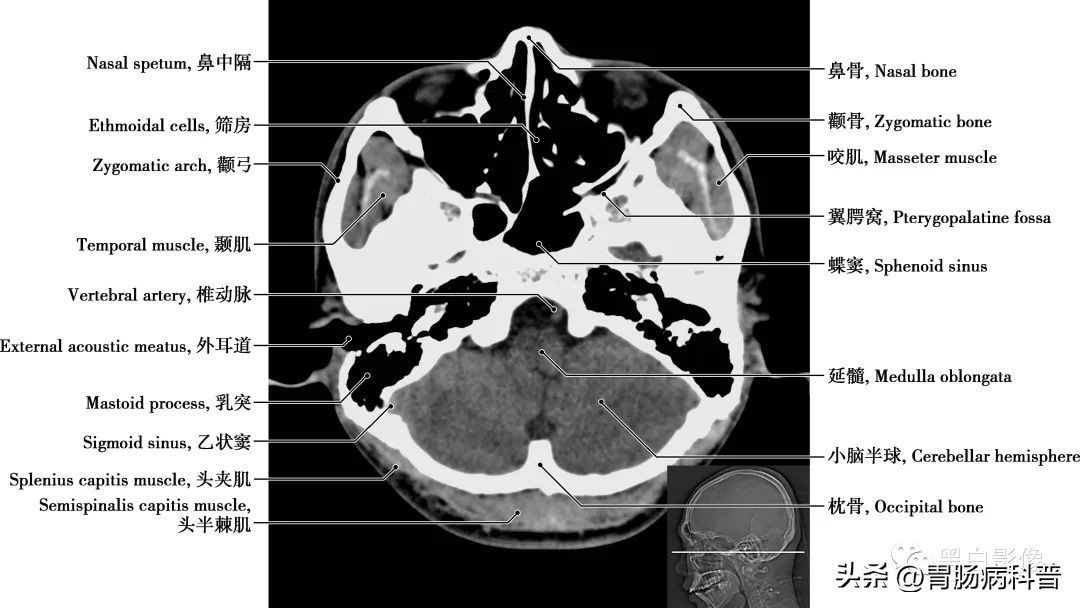

图1-1-16 经第四脑室侧孔轴位切面

翼腭窝 位于颞下窝前内侧,上颌骨(或上颌窦后壁)与翼突之间,前界为上颌骨,后界为翼突及蝶骨大翼前界,顶为蝶骨体下面,内侧壁为腭骨的垂直部。窝内有颌内动脉、上颌神经及蝶腭神经节。翼腭窝向外经翼上颌裂通颞下窝,向内上经蝶腭孔通鼻腔,向前经眶下裂通眼眶,向后上经圆孔通颅中窝,借翼管通颅底外面,向下移行于腭大管、腭大孔通口腔